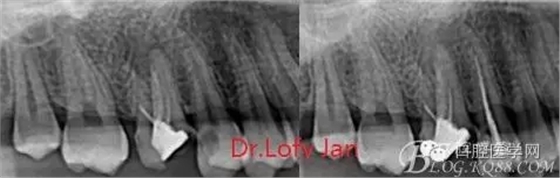

曲面斷層片在未試尖根管治療中的病例整理

前言:自己做的一些曲面斷層片在未試尖根管治療中的病例整理,發(fā)現(xiàn)問題很多包括自身的,技術(shù)的,還有設備的問題,予以總結(jié)整理并期待進一步提高。

病例分析:曲面斷層片在x線輔助診斷與檢查中目前大多數(shù)文獻和著作都建議只能作為初診拍片檢查手段,不能作為終末疾病的確診與手術(shù)療效的評價指標,臨床大部分中小型門診都因為設備不齊全導致信息偏差很大。